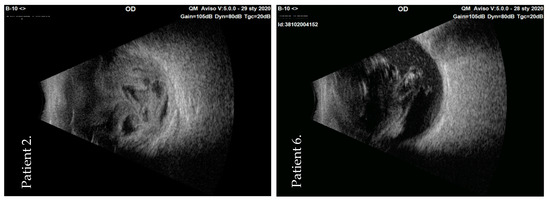

| 6 | F | 85 | Streptococcus mitis/oralis | PPV + vancomycin + silicone oil + anterior chamber rinsing + corneal epithelium abrasion + cataract surgery | LP | HM | Keratic Precipitates | Attached | ||